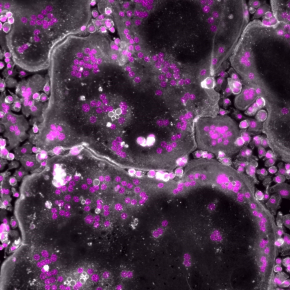

Comme un arbre, le squelette est vivant. Il se développe et doit être taillé pour rester harmonieux. Pour maintenir cet état, les ostéoclastes endossent le rôle de jardinier, élaguant les os usés. Ces grosses cellules, uniques par leur morphologie et leurs fonctions, jouent un rôle crucial dans l’équilibre du squelette, mais aussi dans certaines maladies osseuses, comme l’ostéoporose et le cancer. Une équipe de chercheuses et chercheurs de l’Inserm, du CNRS et de l’Université de Toulouse, en collaboration avec des équipes internationales, vient de mettre en évidence que leur formation et leur activité sont façonnées par une protéine : la moésine. Leurs travaux, publiés dans The Journal of Cell Biology, montrent que celle-ci contrôle la taille des ostéoclastes ainsi que leur capacité à détruire l’os. Ces découvertes ouvrent de nouvelles pistes qui pourraient, à terme, contribuer au développement de traitements innovants contre les maladies osseuses très souvent liées au vieillissement.